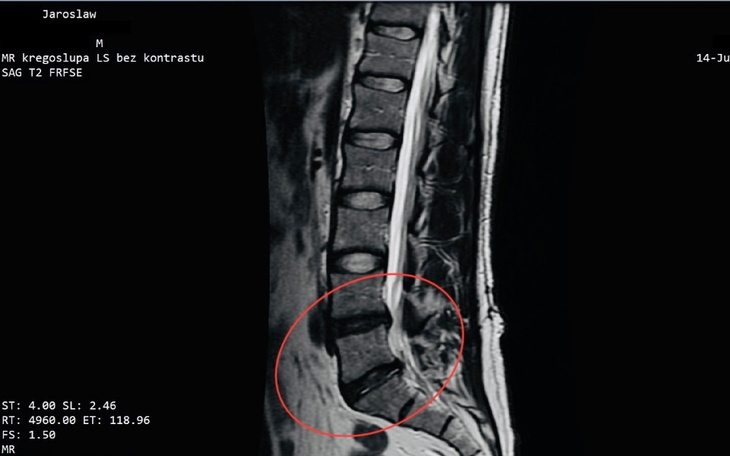

Na obrazach widoczne są znaczące zmiany na poziomie L4/L5 i L5/S1. Według opisu badania, na poziomie L4/L5 doszło do obniżenia wysokości dysku o około 6 mm w porównaniu do stanu sprzed operacji, co powoduje ucisk na korzenie nerwowe. Obecna jest też blizna pooperacyjna, która dodatkowo obciąża kręgosłup, oraz zmiany zwyrodnieniowe kręgów. Na poziomie L5/S1 stwierdzono przemieszczenie materiału dyskowego, ucisk na korzeń L5 oraz obecność torbieli o średnicy około 6 mm, co może prowadzić do dalszych komplikacji.